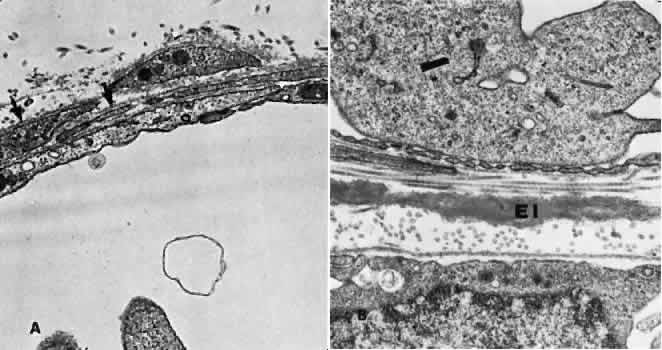

The vessel walls themselves consist of fenestrated endothelium surrounded by a basement membrane and a sparsely arranged layer of pericytes. The portion of the endothelial cell containing the nucleus also contains most of the cell's cytoplasm and organelles. The remainder of the cytoplasm is extremely attenuated, and these regions contain the fenestrae. These fenestrae are approximately 700 to 800 nm in diameter and are covered by a diaphragm. The attenuated areas are most typically found facing the RPE and contain very few pinocytotic vesicles. The region of the cell facing the suprachoroidal space usually contains more cytoplasm, fewer fenestrae, and the nucleus (Fig. 14). Few pericytic processes are seen in cross sections of these vessels on the side of the vessel facing the pigmented epithelium (Fig. 15). However, these processes are more numerous on the surface of the vessel facing the sclera. Because of the fenestrae, the choriocapillaris actively leaks fluorescein molecules.

Fig. 14. Electron micrograph. A. A portion of the capillary wall facing the suprachoroidea. The endothelial layer is relatively thick, and few fenestrae are present. Several pericytic processes (arrows) may be seen. B. A portion of the capillary wall facing the pigmented epithelium. Numerous fenestrae may be seen in the attenuated endothelium. The elastica of Bruch's membrane is well developed (EI).

Fig. 15. Electron micrography of a tangentially sectioned choroidal capillary. The attenuated portion of the endothelial cell may be seen facing the elastica of Bruch's membrane (arrows).